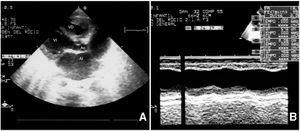

Con 19 días de vida se objetivó una ectasia coronaria izquierda cuyo calibre era de 4 mm (> 3 DS; fig. 3) instaurándose tratamiento con gammaglobulina i.v. (2 g/kg/24 h), repetida en un segundo ciclo a la semana del primero, y aspirina (40 mg/kg/día 2 semanas, pasando a 5 mg/kg/día durante 3 meses).

Figura 3. Dilatación de la arteria coronaria izquierda (19 días de vida): ecocardiografía 2D, proyección paraesternal del eje corto inmediatamente por encima de la válvula aórtica. Obsérvese que la dilatación es exclusiva del tronco común de la arteria coronaria izquierda después de su bifurcación, el calibre de la arteria descendente anterior y circunfleja es normal.